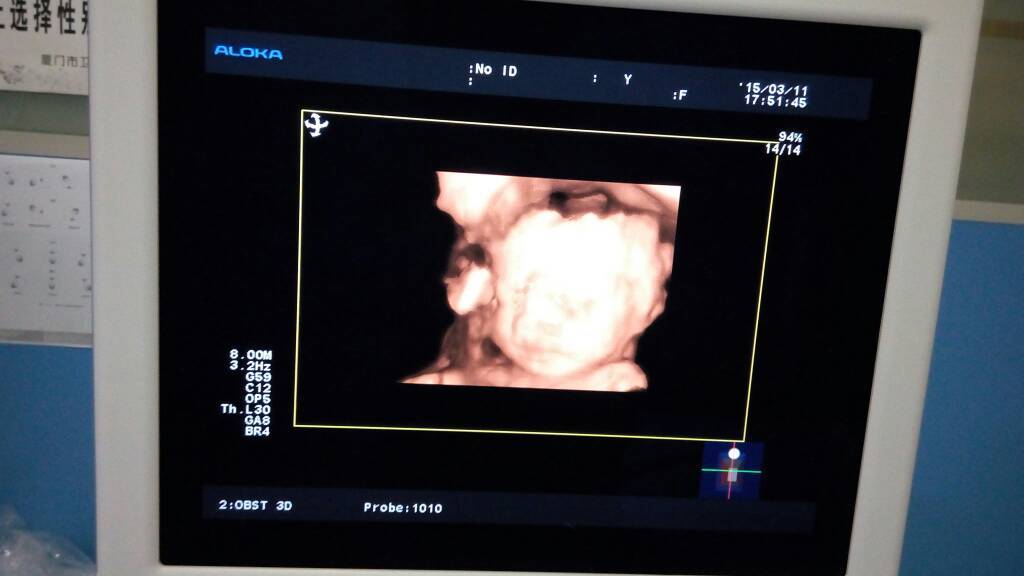

三维照片,亲们看看像男孩还是女孩 三维照片,亲们看看像男孩还是女孩 点击展开 珠宝贝儿 2015-03-12 02:08 为您推荐: 其他回答 健康就好! 158*****123_rFrj 2015-03-12 13:46 看不出来! 好运来_eVgW 2015-03-12 05:25 像男孩,听说前避后避的区分男女 丫头_vDQp 2015-03-12 03:31 不管是什么都好,你说是不是 吖_H4Ir 2015-03-12 03:01 祝宝妈好孕 小闹闹的妈妈i 2015-03-12 03:00 加载更多 相关问题 今天做了三维彩超大家帮忙看看,能看出男孩女孩吗?BPD:63 HC; 236 AC;200 我老公喜欢女儿 你们帮我看看女孩子还是男孩子 亲 胎囊11×8×6mm是男孩还是女孩、帮忙给看看亲们